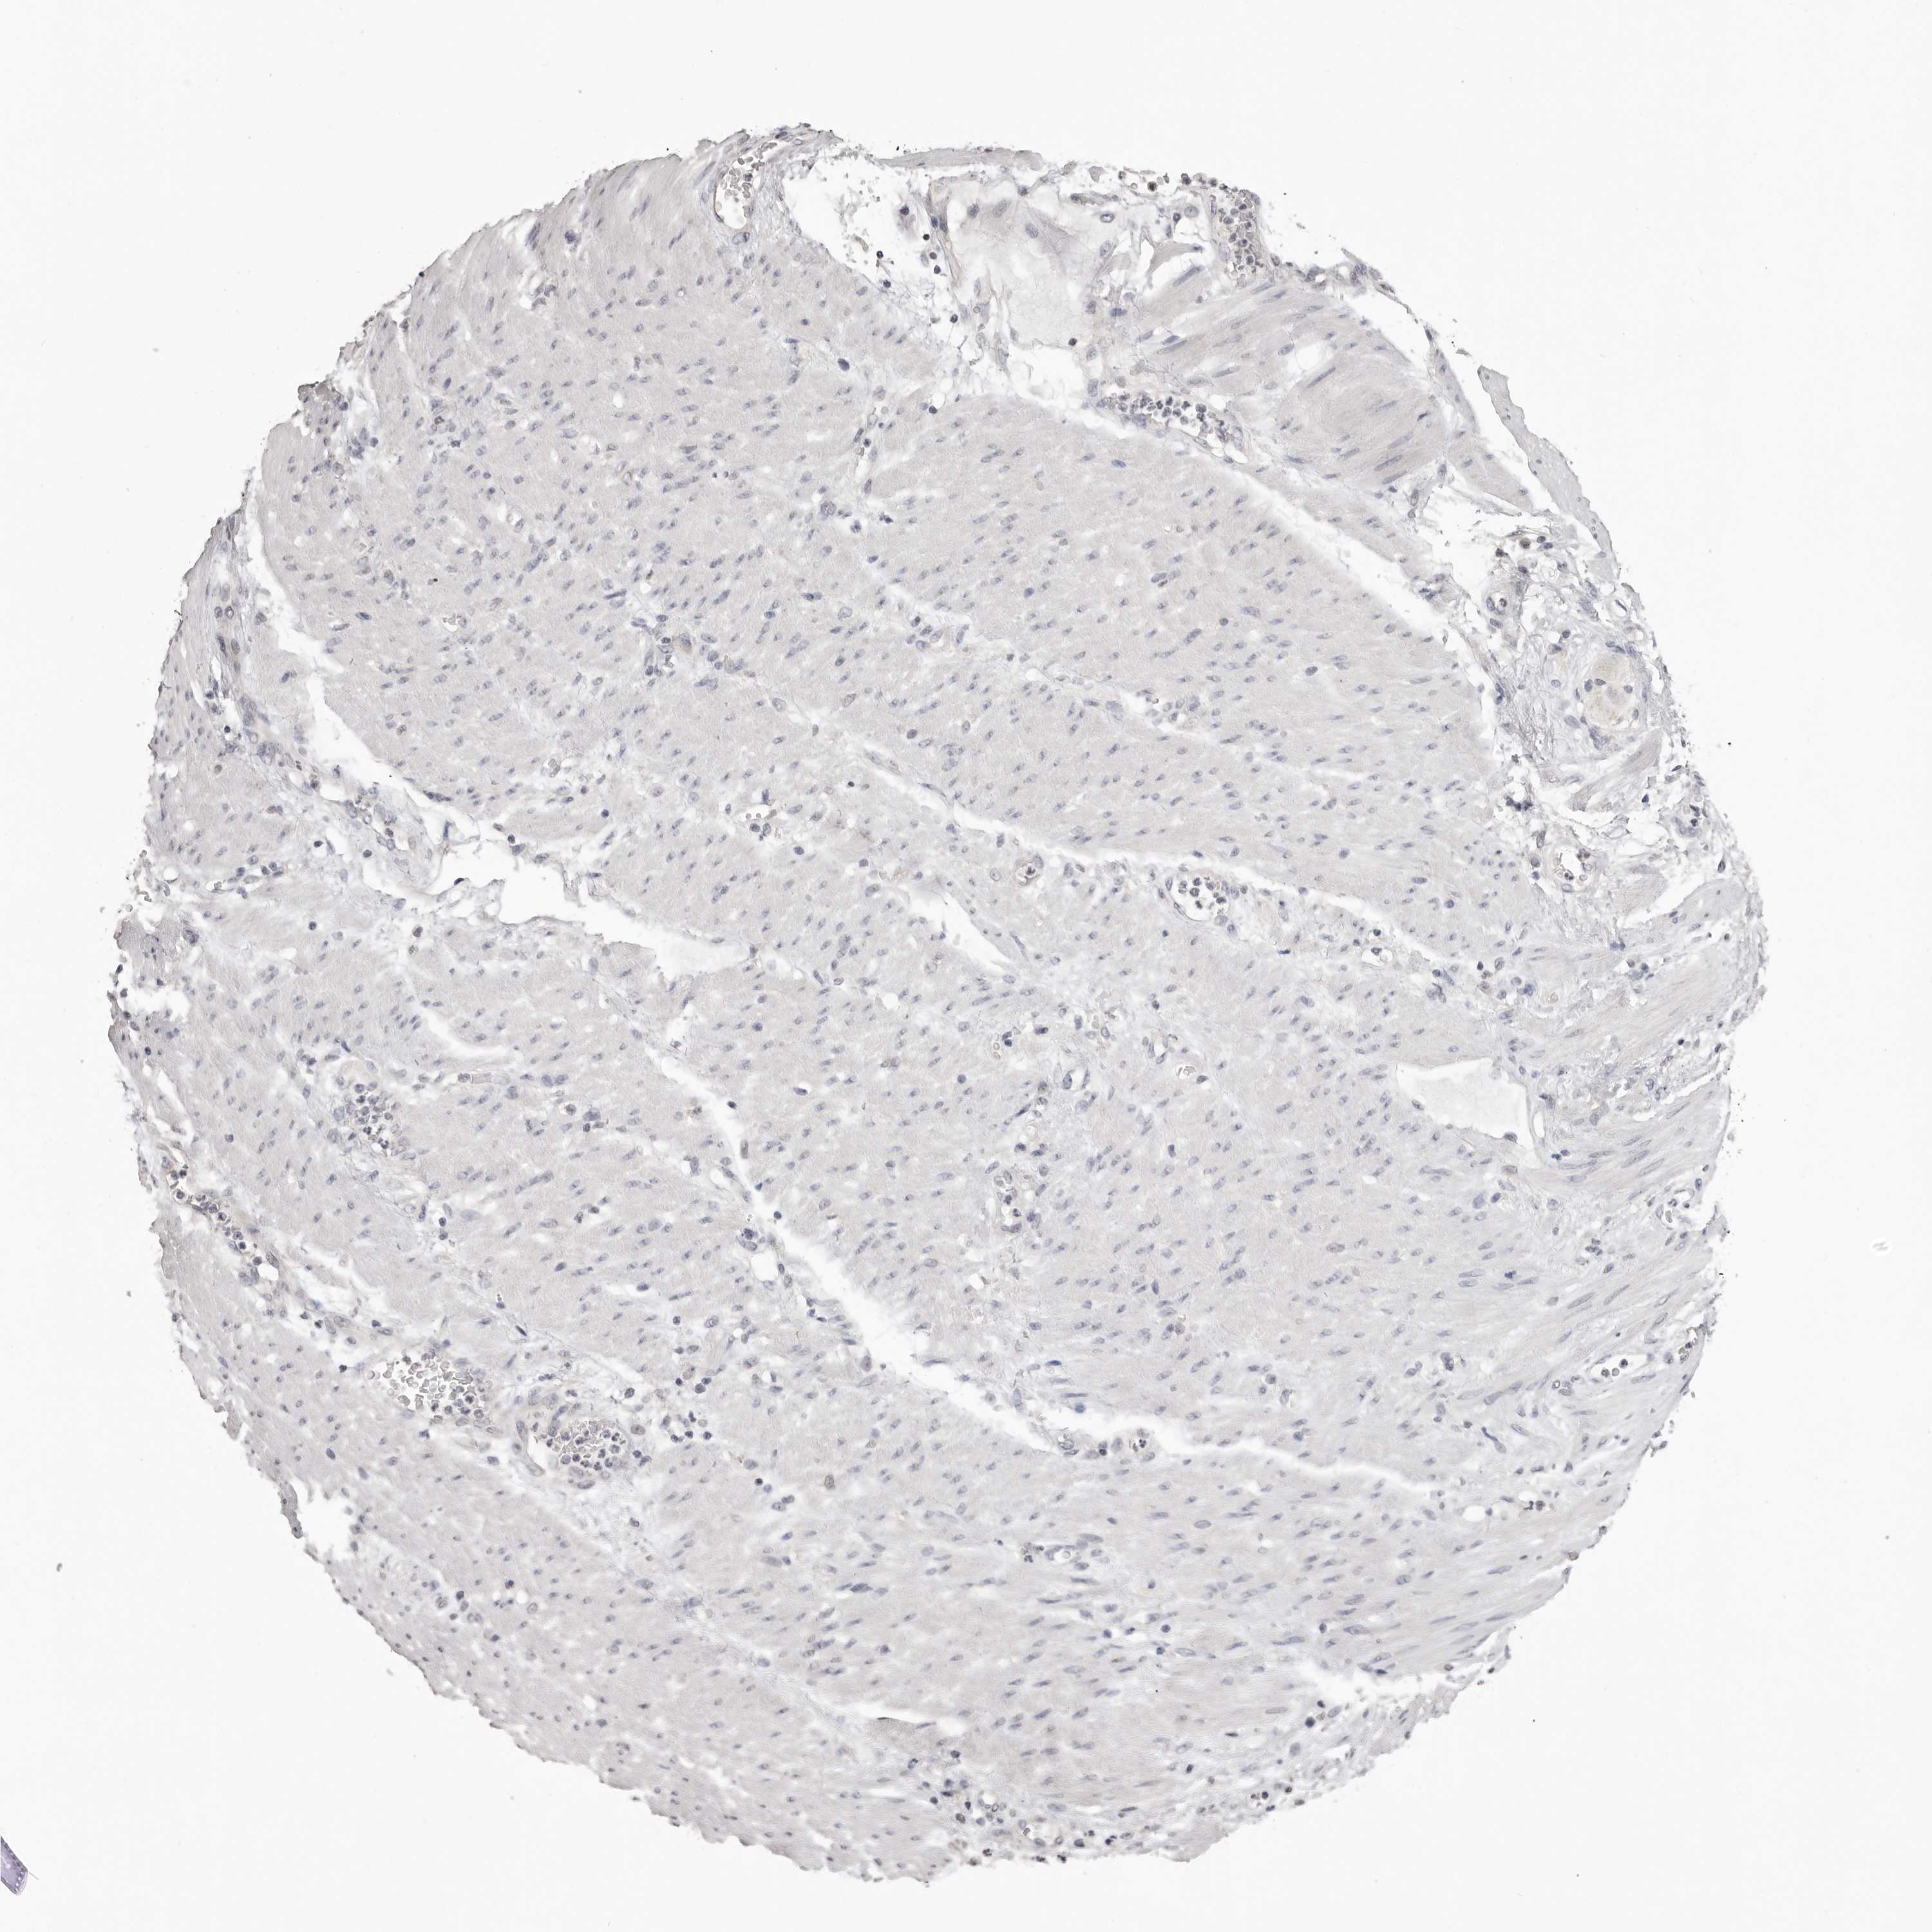

STOMACH CANCER - Protein expressioni

A mouse-over function shows sample information and annotation data. Click on an image to view it in a full screen mode. Samples can be filtered based on level of antibody staining by selecting one or several of the following categories: high, medium, low and not detected. The assay and annotation is described here.

Antibody stainingi

Antibody staining in the annotated cell types in the current human tissue is reported as not detected, low, medium, or high, based on conventional immunohistochemistry profiling in selected tissues. This score is based on the combination of the staining intensity and fraction of stained cells.

Each image is clickable and will lead to virtual microscopy that enables deeper exploration of all samples and also displays staining intensity scores, fraction scores and subcellular localization as well as patient and tissue information for each sample.

Antibody HPA028059

Staining

High

Medium

Low

Not detected

Intensity

Strong

Moderate

Weak

Negative

Quantity

>75%

75%-25%

<25%

None

Location

Nuclear

Cytoplasmic/membranous

Cytoplasmic/membranous,nuclear

Adenocarcinoma, NOS